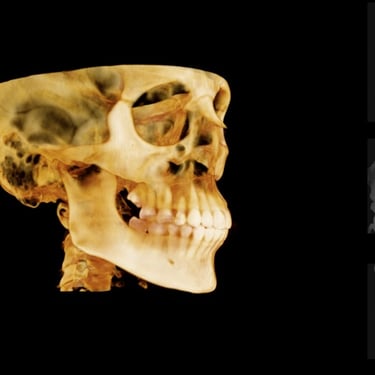

Implant Dentistry/Dental Implants

Implant planning using CBCT Single/Multiple teeth implants All on 4 and All on 6 Sinus lift: direct & indirect Ridge split using Piezo surgery Bone Grafting Soft tissue grafting A-PRF, I-PRF